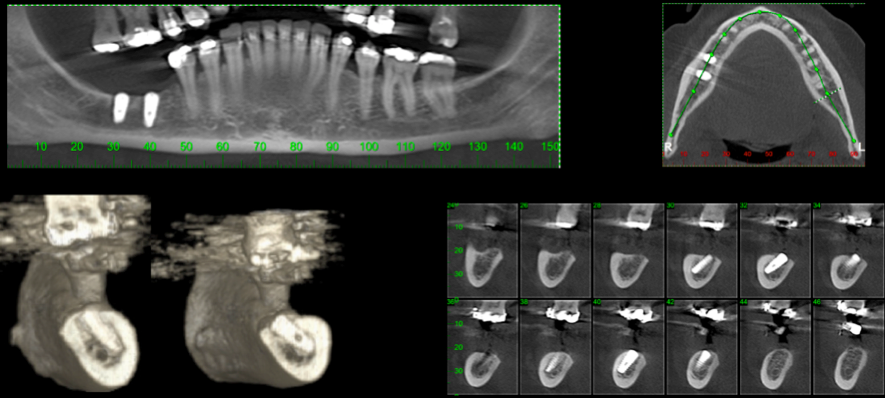

Paciente do sexo feminino, 52 anos, solicitou tratamento devido a aparência insatisfatória dos dentes, além da função mastigatória limitada. O tratamento foi iniciado na região posterior esquerda da mandíbula, a fim de garantir suporte para a futura reabilitação. O exame de tomografia computadorizada revelou altura óssea entre a crista e o canal mandibular insuficiente para colocação de implantes convencionais. Foi planejado a colocação de implantes na região vestibular do canal, com mínima distância do canal propriamente dito.

Fig. 1 e 2 Tomografia inicial

Fig 8 Tomografia final: observar os implantes em relação ao nervo alveolar